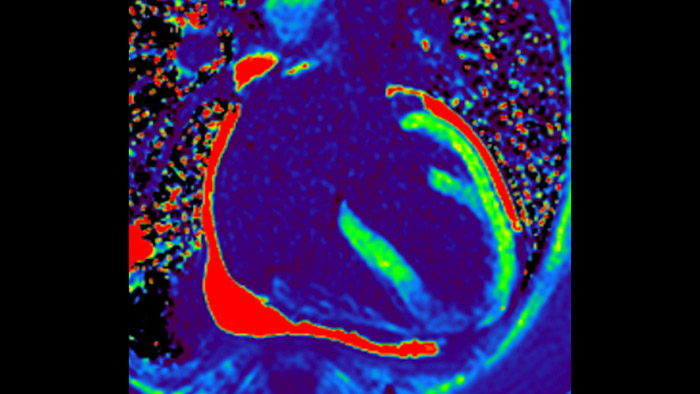

Visualize and evaluate blood flow

Visualise and evaluate blood flow

IntelliSpace Portal MR Caas5,6 4D Flow post-processing solution enables generation of 3D volume reconstructions, to visualise and evaluate blood flow in cardiovascular structures, including heart valves, chambers, and vessels, based on cardiovascular MR 4D Flow imaging.